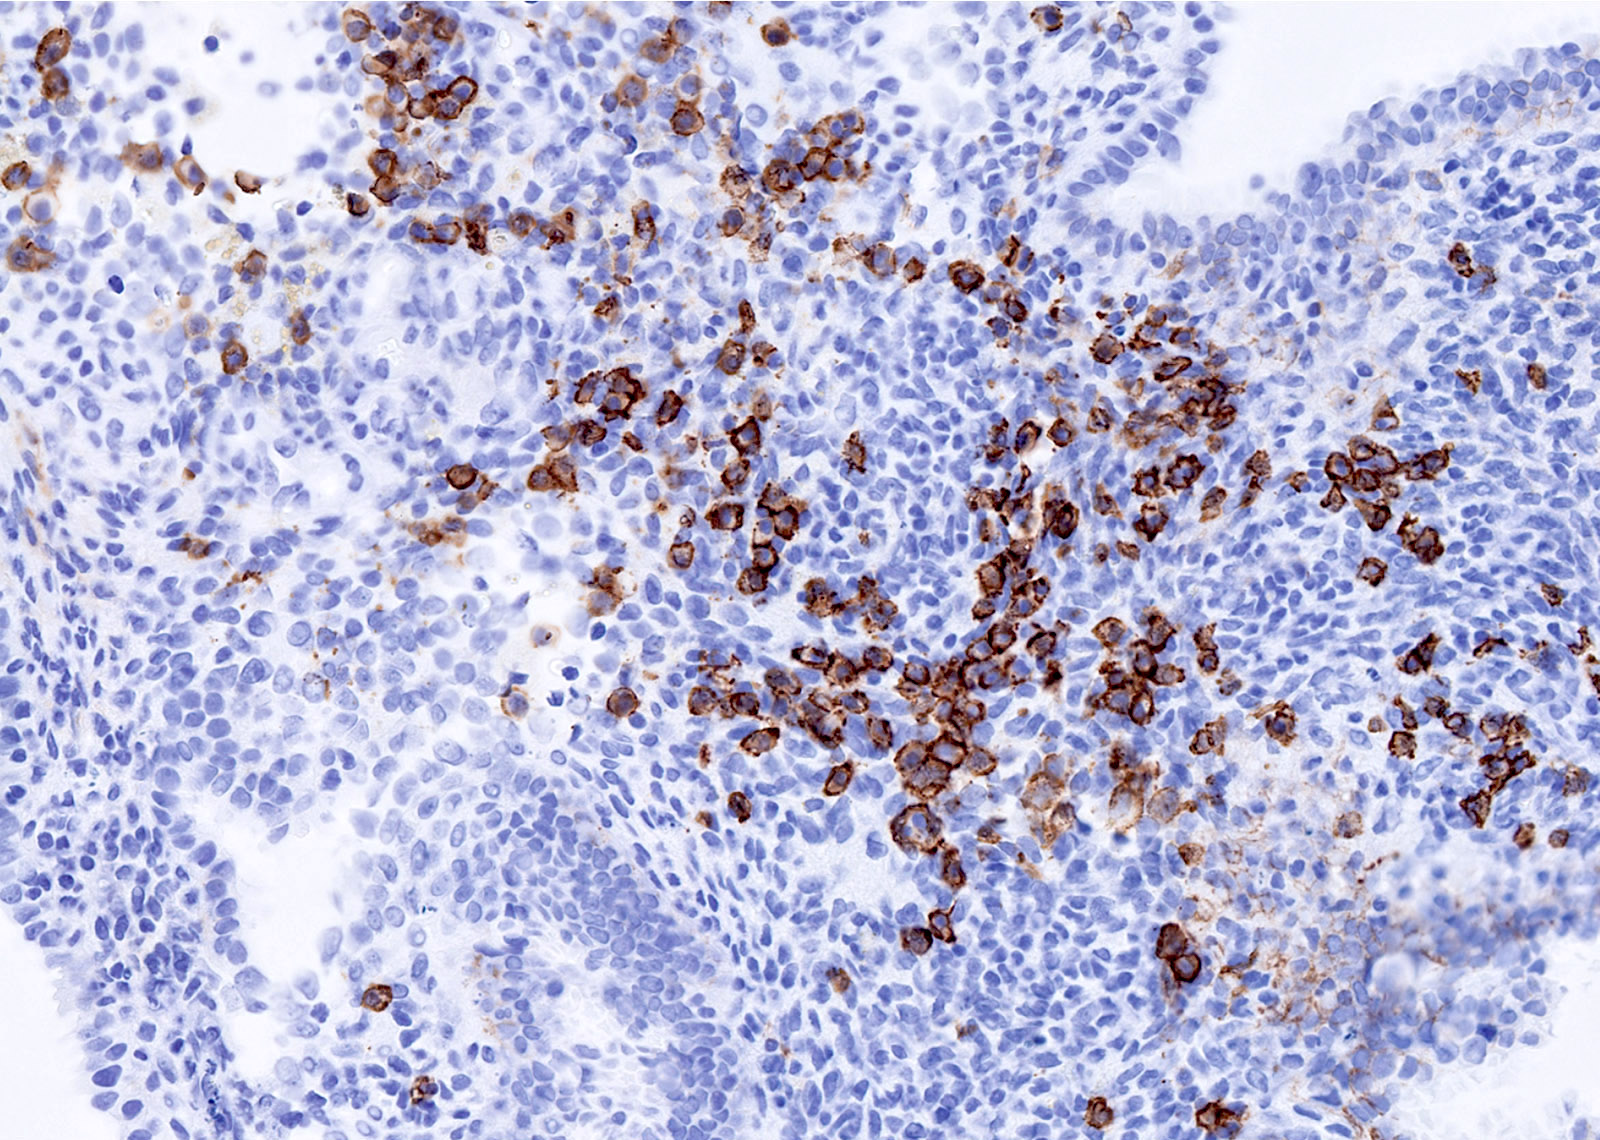

Microscopic (histologic) images

Contributed by Stephanie L. Skala, M.D. and Yuri Tachibana, M.D.

Chronic endometritis

Positive stains

- Chronic endometritis

- CD138 / syndecan in plasma cells (Arch Pathol Lab Med 2004;128:1000)

- MUM1 in plasma cells; higher sensitivity, cleaner background (Int J Surg Pathol 2019;27:372)